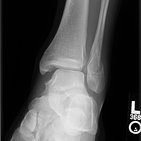

Auf diesem Bild schauen wir in einer Frontalansicht, also von vorne, auf das rechte Sprunggelenk. Ihr erkennt bestimmt sofort, dass es aus mehreren Gelenkverbindungen besteht. Verschiedene Knochen sind an der Bildung dieses Gelenks beteiligt. Sie werden durch viele Ligamente, sprich Bänder, zusammengehalten.